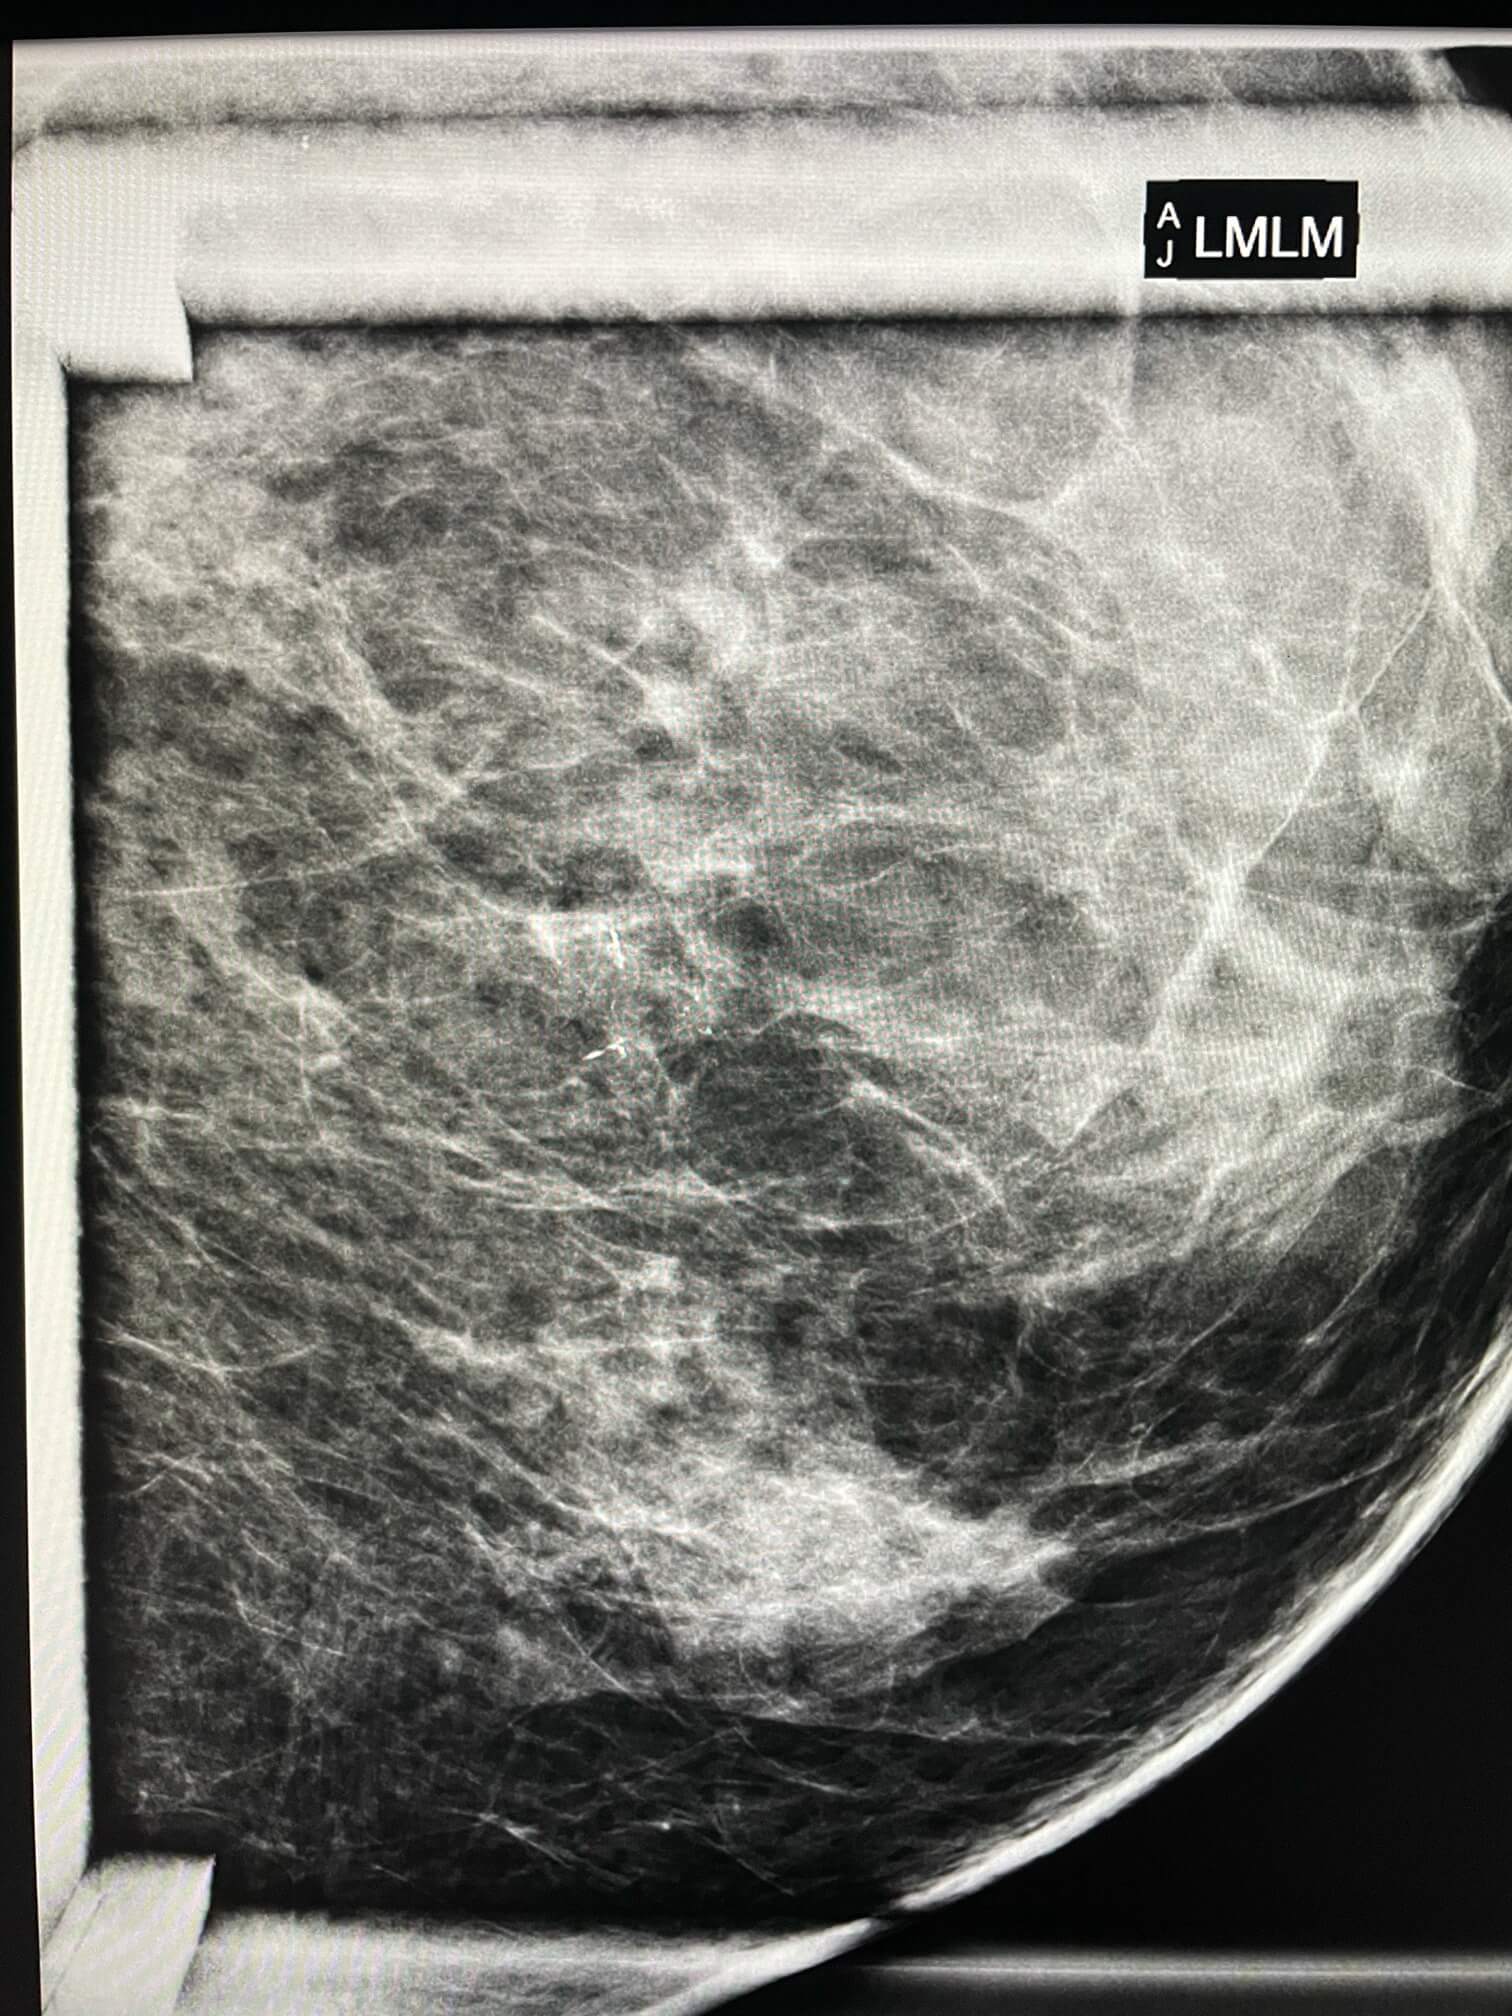

57-year-old female, prep mammogram.

MammoScreen™ points to a focus of microcalcifications consisting of a dozen or so polymorphic microcalcifications, irregular (red flag).

This focal spot was not present on the previous mammogram.

A stereotactic biopsy of the microcalcification identifies a grade 2 intra-ductal carcinoma.